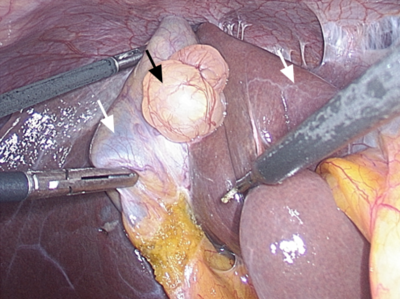

Í kjölfarið var konunni vísað til kviðarholsskurðlækna á Landspítala, þar sem farið var yfir niðurstöður myndgreininga og niðurstaðan sú að einkenni gætu vel tengst umræddri blöðru. Hún gekkst undir gallblöðrutöku nokkrum mánuðum síðar og gekk aðgerð vel. Í aðgerðinni var þess gætt að rjúfa ekki umrædda blöðru þar sem vefjasýni lá ekki fyrir. Útlit gat hins vegar samrýmst gallblöðrusarpi (Mynd 2). Gallblaðra var send í vefjarannsókn. Blaðran mældist 24x14x12 mm og var áföst vegg gallblöðrunnar á um 17x5 mm svæði (Mynd 3). Engin merki sáust um blöðruna á innanverðri gallblöðru. Við opnun á blöðrunni sást ljósgrænn vökvi og var blaðran með skilrúmum sem skipti henni upp í tvö til þrjú hólf. Veggþykkt blöðrunnar mældist innan við 1 mm. Við smásjárskoðun sást að sarpurinn var klæddur útflatri, góðkynja þekju og sáust sléttar vöðvafrumur í vegg sarpsins. Vefjagreining sýndi því fram á að um væri að ræða raunsarp (Mynd 4). Gangur eftir aðgerð var án fylgikvilla, hún varð einkennalaus og útskrifuð úr eftirliti.

Mynd 2. Mynd úr aðgerð þar sem sjá má blöðruna (svört ör) á milli gallblöðru (hvít ör, vinstri) og lifrar (hvít ör, hægri).